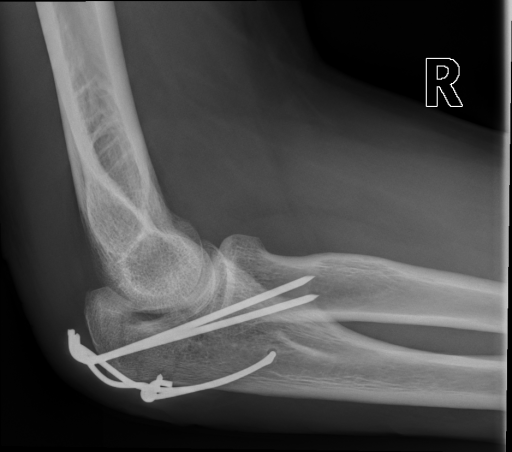

The IRMA dataset, supplied for the imageCLEF organization, had annotated codes were similar to domain expert knowledge [9, 12, 13, 14]. This database has been used by many researchers and is comprised of preset test and training portions, which enable direct comparisons of metrics. The IRMA codes (manually created by several clinicians) contains information on technical, biological and diagnostic traits of the image in a structured manner: TTTT-DDD-AAA-BBB. Each section is hierarchical meaning there is a least significant bit and most significant digit (Table 1). Sample IRMA images are depicted in Fig. 1.